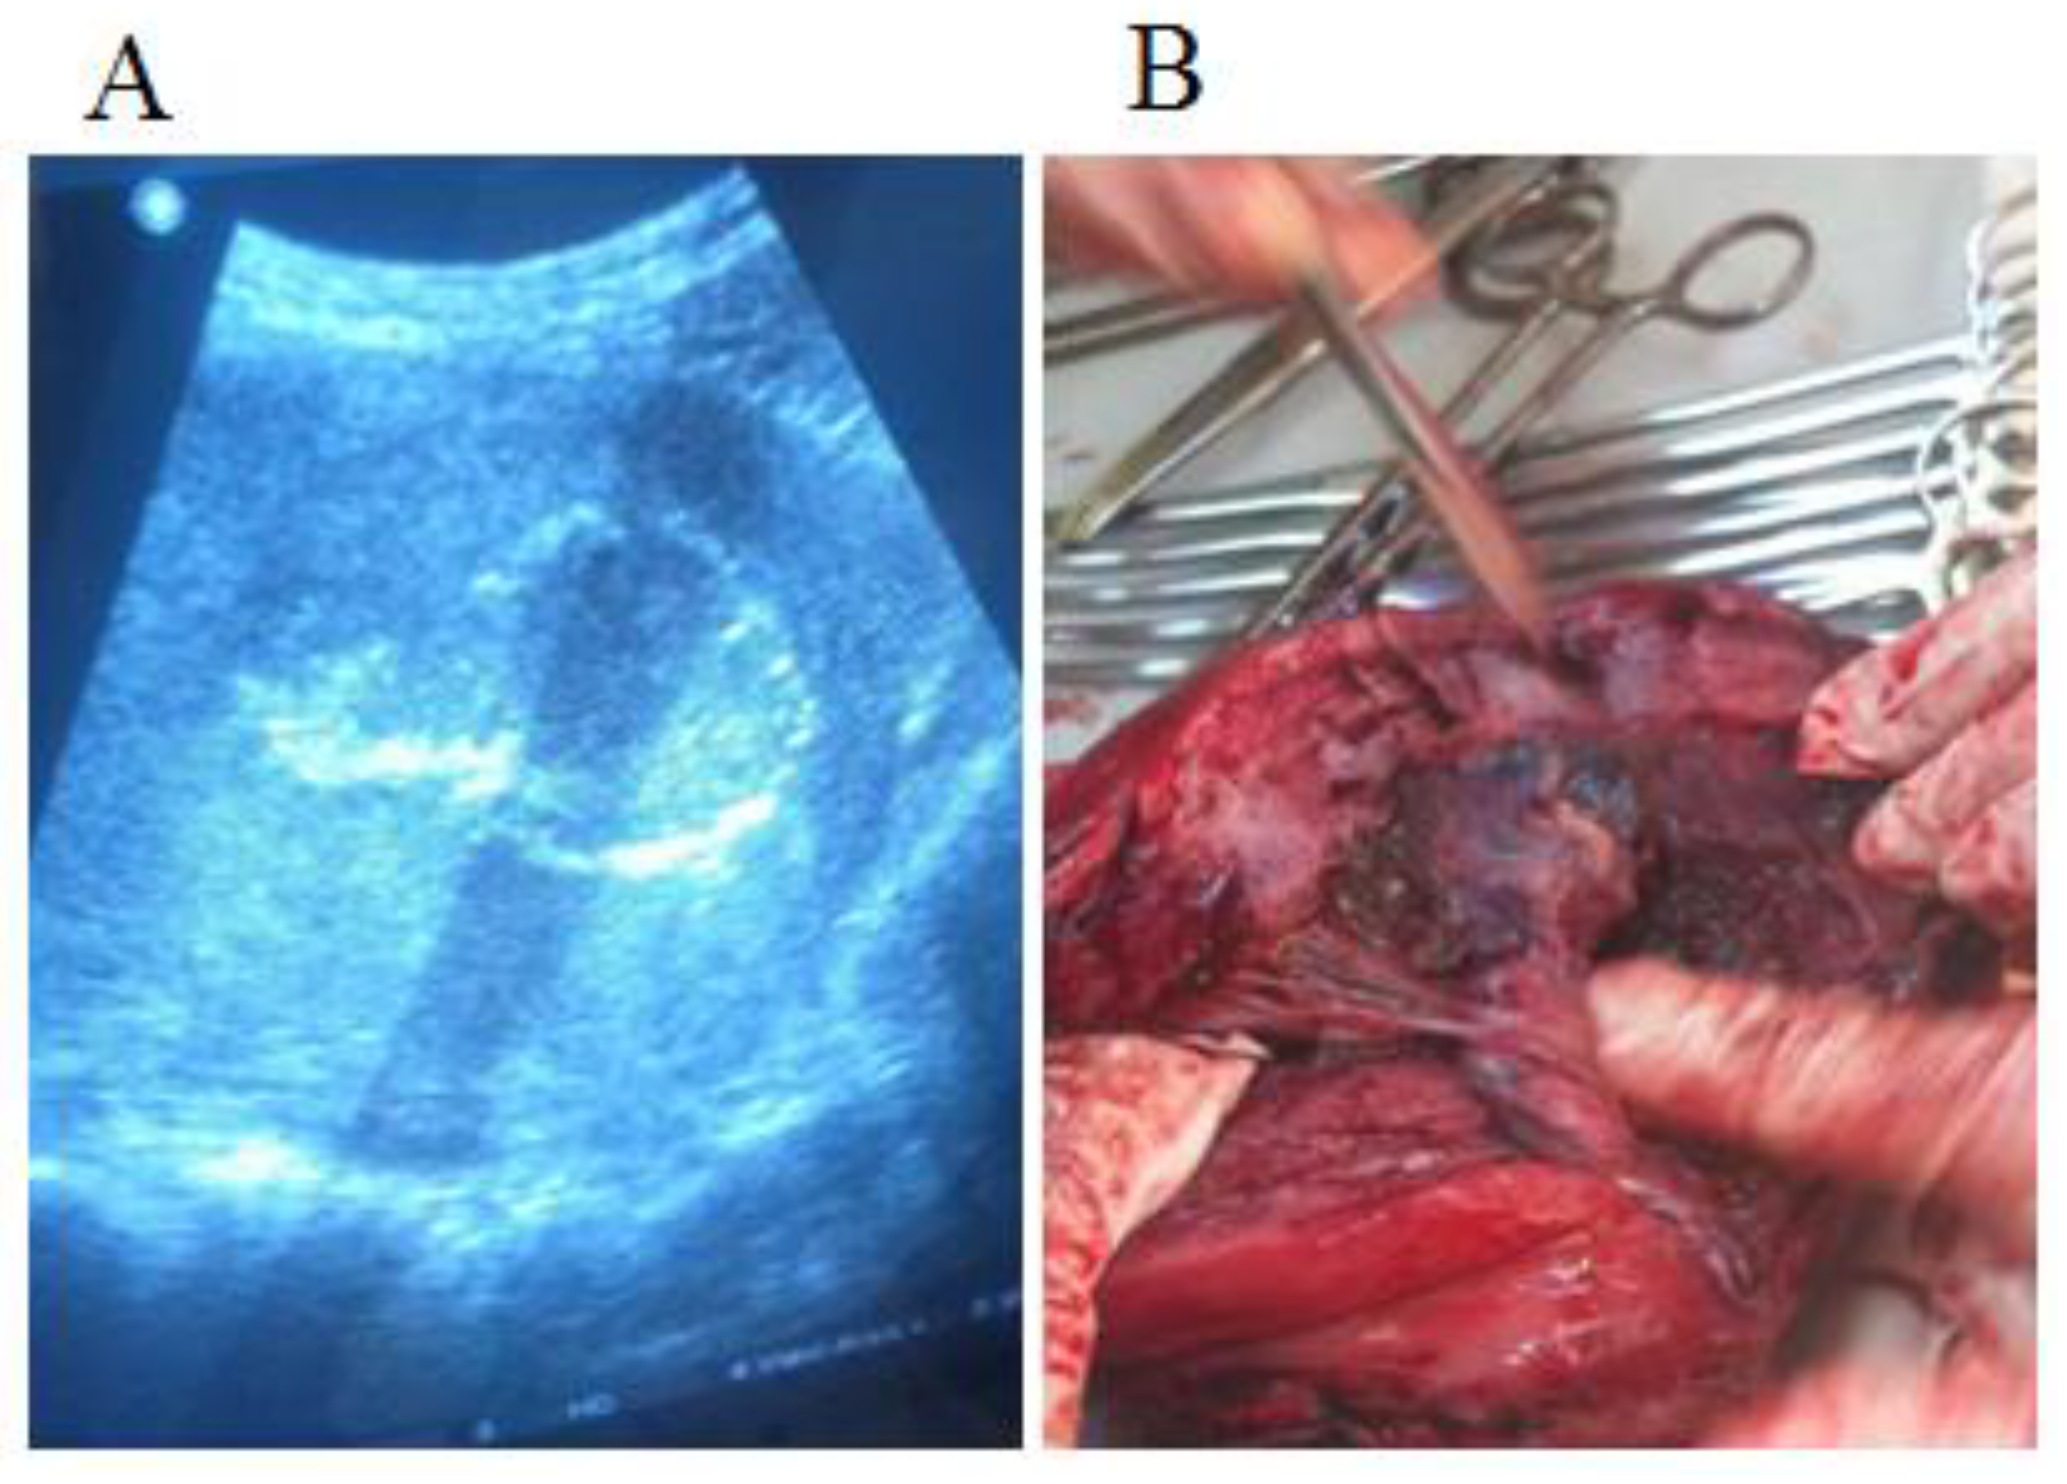

Maternal morbidity from placenta previa is primarily related to antepartum and/or postpartum hemorrhage, blood transfusions, and subsequent emergency peripartum hysterectomy (EPH) (Figure 3, a-b). On a sample of 13.162 patients who underwent cesarean or vaginal delivery in Bucur Maternity Hospital over 6 years (from 2010 to 2015), 12 cases were encountered in which one or more of the risk factors that lead to EPH were found [21].

In the current study, complications were related to both fetal and maternal counterparts, with 4 EPH, one fetal death, and no maternal mortality. Three of four EPH were performed for percreta situations and led to 75% morbidity in those cases. We found no usual ICU admission, excepting the C-sections complicated with EPH, when a 2-3 days period of intensive care was necessary for adequate monitoring. Depending on the hemoglobin value, patients with values between 7 and 9mg/dl were administered ferrous supplements to correct anemia. For all patients with values below 7mg/dl, blood transfusion (1-2 U.I.) was performed. Only one fetal death was registered due to an extreme prematurity associated the Down syndrome.

Figure 3. The hysterectomy piece for placenta accreta (A); The ultrasound before the intervention (B).